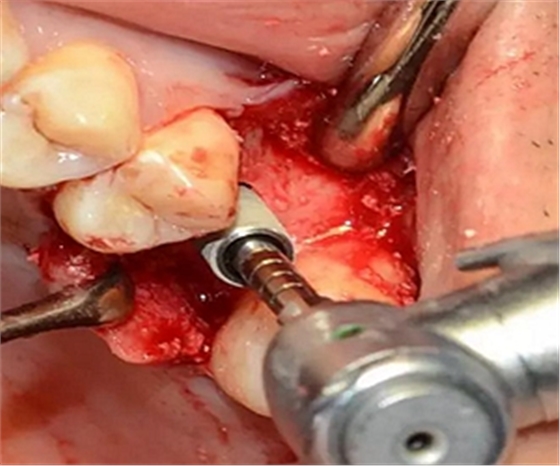

定點(diǎn)定向,初步擴(kuò)孔

使用止停環(huán)控制深度,逐級(jí)預(yù)備打開嵴頂入路。探之竇膜力反饋正常,呈持續(xù)張力。手動(dòng)探查分離通路周圍竇粘膜并略提升。

用配套工具進(jìn)行水壓式?jīng)_頂,提升竇膜。手感力反饋和回吸正常。在沖壓水量上要控制,緩慢反復(fù)多次抽吸,確保竇粘膜提升均勻。

提升時(shí)相關(guān)步驟可參考下面圖片